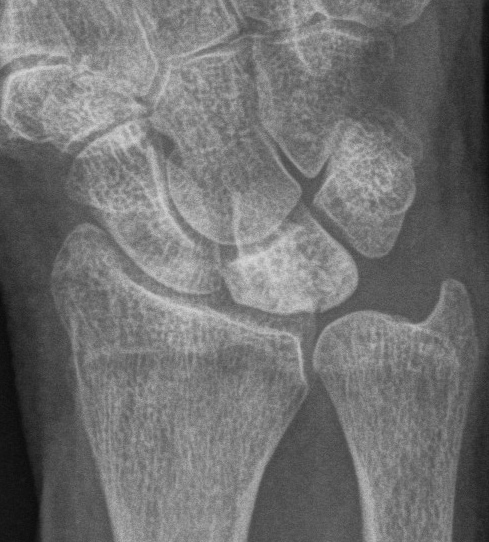

| Stage IIIB | Stage IV |

|

Collapse / fragmentation Scaphoid flexed / Capitate migrates proximally |

Pancarpal osteoarthritis |

![]() |